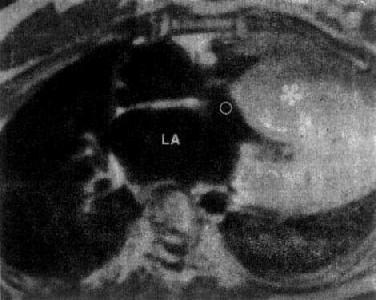

图3-2-27 左心室室壁瘤

MRI显示左心室室壁瘤(↑),呈心壁变溥,局限性膨隆

图3-2-28 特发性心肌病

心MRI,SE序列横断面图像,左心室壁及室间隔肥厚(*),LA左心房